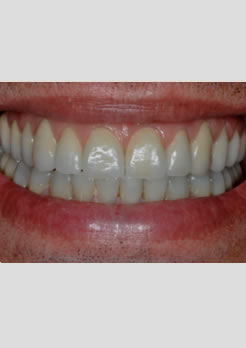

Prótese fixa instalada dois dias após a colocação dos implantes

Novo perfil rejuvenecido